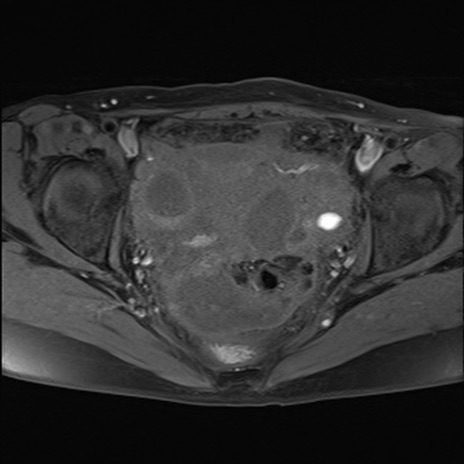

症例39 脂肪抑制T1WI(横断像)

MRI(4日後)

T1WI(横断像)